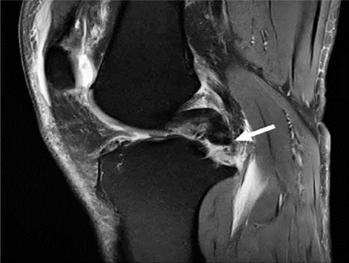

Hình 6. Nốt sần sụn chêm. Hình ảnh pd sagittal cho thấy một nốt sần hình sụn (mũi tên) ở vùng của rễ sụn trung gian sừng sau.

Các nốt sần ở phía trước hoặc phía sau được thấy ở 97% bệnh nhân có sụn chêm bên bình thường [10], và do đó, việc không hình dung được các nốt sần có thể làm tăng nghi ngờ về một vết rách sụn chêm bên cơ bản (Hình 6) [10]. Sự vắng mặt của các nốt sần cũng đã được báo cáo ở những bệnh nhân bị ung thư biểu mô bên tăng vận động có triệu chứng [11].